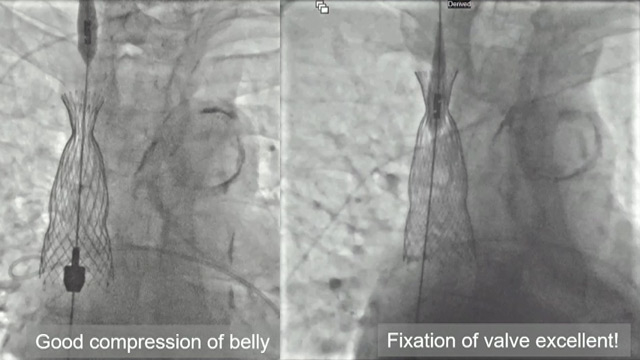

TAVI and Mitral: Advanced techniques for complex valve interventions

Delve into this captivating session showcasing a diverse range of TAVI and mitral valve interventions from the AICT-AsiaPCR 2024 conference. Witness the navigation of complex cases, including a mitral valve-in-ring procedure, a percutaneous mitral commissurotomy in a pregnant patient, and the management of unexpected complications during...